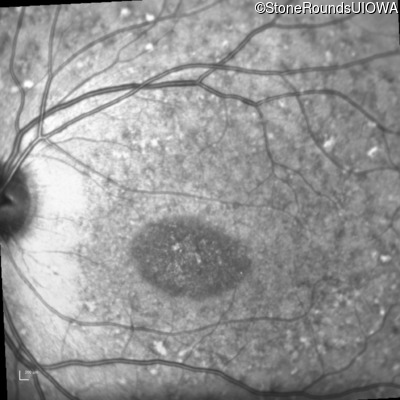

Infrared Fundus Photograph - Right - 20/125 sc

Exemplar